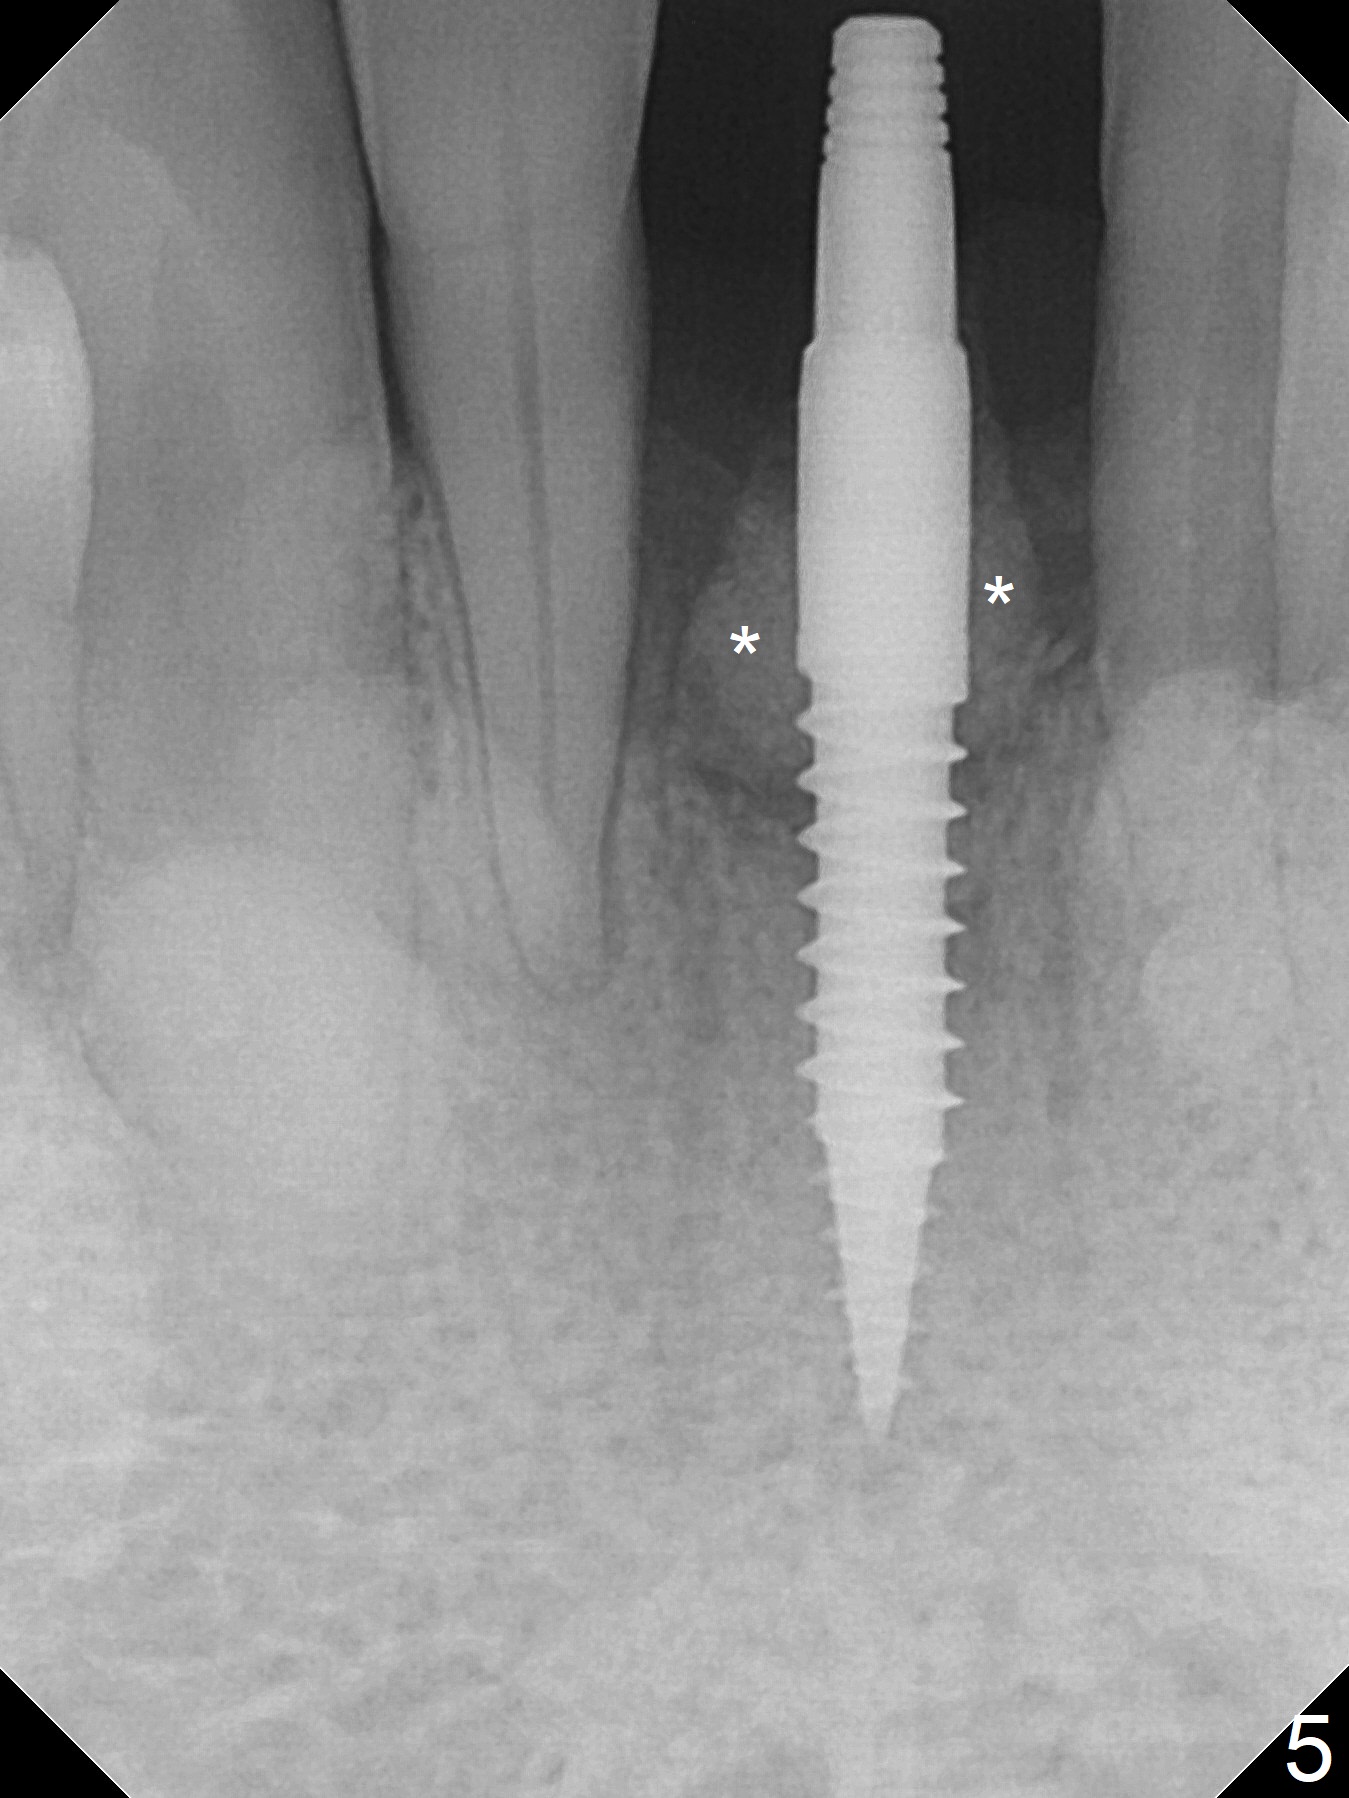

When the patient returns for implant placement 1.5 years after the last treatment (SRP), the tooth #25 has exfoliated, whereas the tooth #24 is severely displaced (Fig.1-3). In fact the buccolingual plates are found to be lost after extraction, corresponding to change in gingival color indicated by an arrowhead in Fig.1. Initial osteotomy with 1.2 mm drill is parallel to the terminal branches of the Incisive Canal (Fig.4 arrowheads). Since the gingiva is as thick as 7.5 mm (Fig.3 arrow), a 3x14 mm 1-piece implant with 4 mm cuff is placed (Fig.5); three implant threads are outside the native bone; with allograft (*) placed and the neighboring crests being coronal to the threads, the chance of periimplantitis should be remote. An immediate provisional is fabricated to contain the graft in place. Meanwhile the tooth #2 is symptomatic with crack. The top 3 threads appear to be contacted by the newly formed crestal bone 6 months postop (Fig.6 *). Bone appears to have grown into the space between implant threads 6 months post cementation (13 months postop).